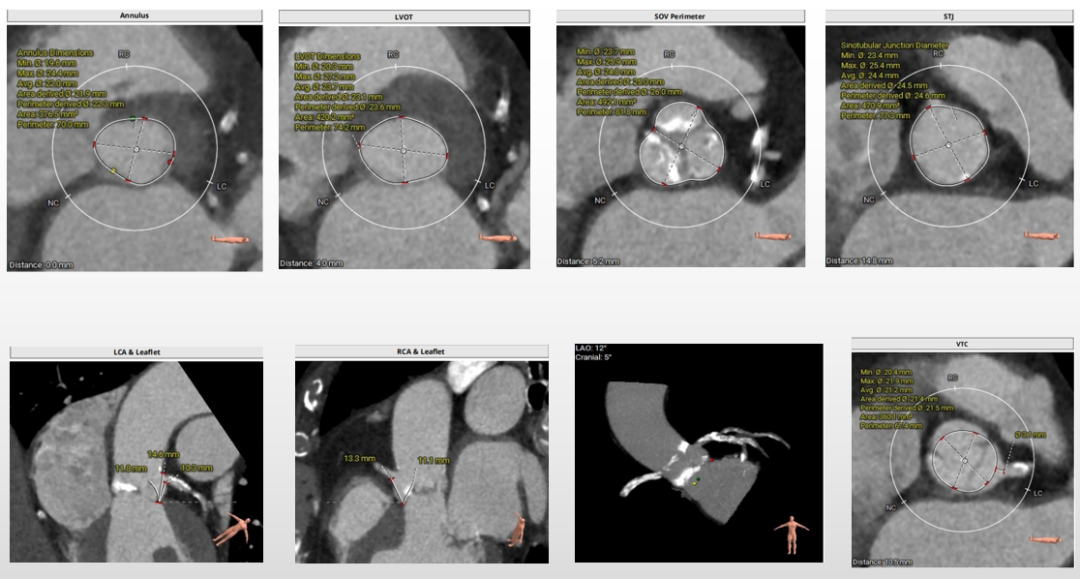

第一例术前评估

主动脉根部评估

三叶式主动脉瓣,瓣叶增厚,流出道呈敞口状,左右冠均有钙化,由于瓦氏窦、STJ内径小,左冠窦瓣叶长度>瓣叶附着缘到冠脉开口的距离,VTC3.1mm,术中冠脉阻挡风险较高。

瓣环上解剖结构评估

中度钙化,瓣上6-8mm限制最重,根据瓣环及瓣上情况,选18mm球囊预扩、AV23瓣膜。